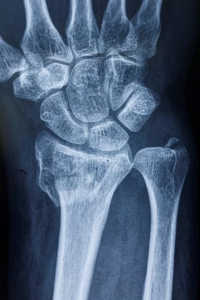

Yarıçap, ön koldaki iki kemikten biridir ve elin başparmak tarafında bulunur. Yarıçapın karpal kemiklerle eklemlenerek bilek eklemini oluşturan kısmına distal uç denir. Yarıçap bu bölgede kırıldığında, distal yarıçap kırığı meydana gelir .

Distal radius kırığı tipik olarak kemiğin ucundan yaklaşık bir inç uzakta meydana gelir. Kendi başına veya distal ulnadaki (küçük önkol kemiği) bir kırıkla birlikte meydana gelebilir.

Doktor tanıyı doğrulamak için el ve bilek radyolojik taramaları isteyecektir. En popüler ve yaygın olarak kullanılan tanısal görüntüleme yöntemi X ışınlarıdır. X ışınları, kemiklerin gerçekten kırılıp kırılmadığını ve bunların yer değiştirmiş kırıklar olup olmadığını ortaya çıkarabilir . Ayrıca kaç tane kırık kemiğin mevcut olduğunu da gösterebilirler.